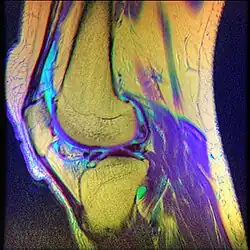

O diagnóstico mais detalhado é feito, normalmente, através de um exame de Ressonância Magnética[28] e testes físicos realizados por fisioterapeutas,[6] além de fazer uma avaliação com um reumatologista, um fisiatra, um ortopedista, para receber o diagnóstico preciso e o tratamento correto.[29] Pode ser utilizado também, durante avaliação fisioterapêutica, escalas e testes funcionais para identificar o nível de impacto dessa dor e disfunção, no dia-a-dia do indivíduo.[30]